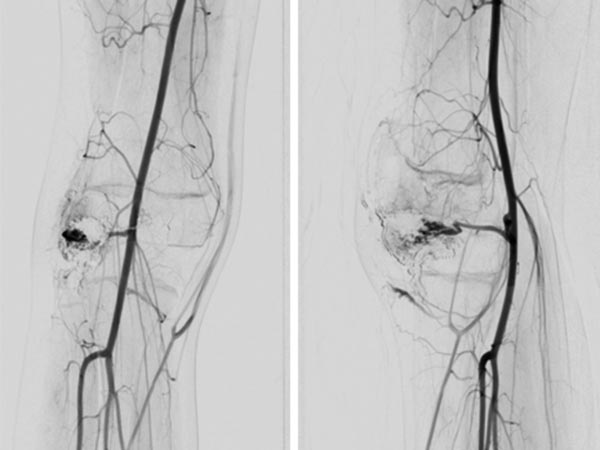

Abschluss-DSA-Bild (links a.-p., rechts seitliche Projektion) nach Beendigung der erneuten Embolisation zeigt wiederum angiographisch einen vollständigen Verschluss der beiden Anteile der AVM.